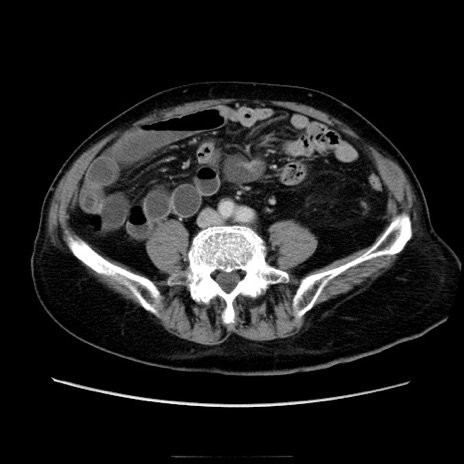

症例21(横断像)

【症例】70歳代男性

【主訴】腹痛

【現病歴】肝硬変・肝細胞癌にてかかりつけの方。約9時間前に食後より腹痛出現。症状が徐々に増悪し、嘔吐出現したため来院。

【既往歴】肝硬変、肝細胞癌(RFA、TACE後)

【身体所見】意識清明、表情苦悶様、BT 36℃、BP 129/78mmHg、P 88bpm、SpO2 97%(RA)、右上腹部から心窩部にかけて圧痛あり、反跳痛なし、筋性防御あり。

【データ】WBC 5800、CRP 0.16